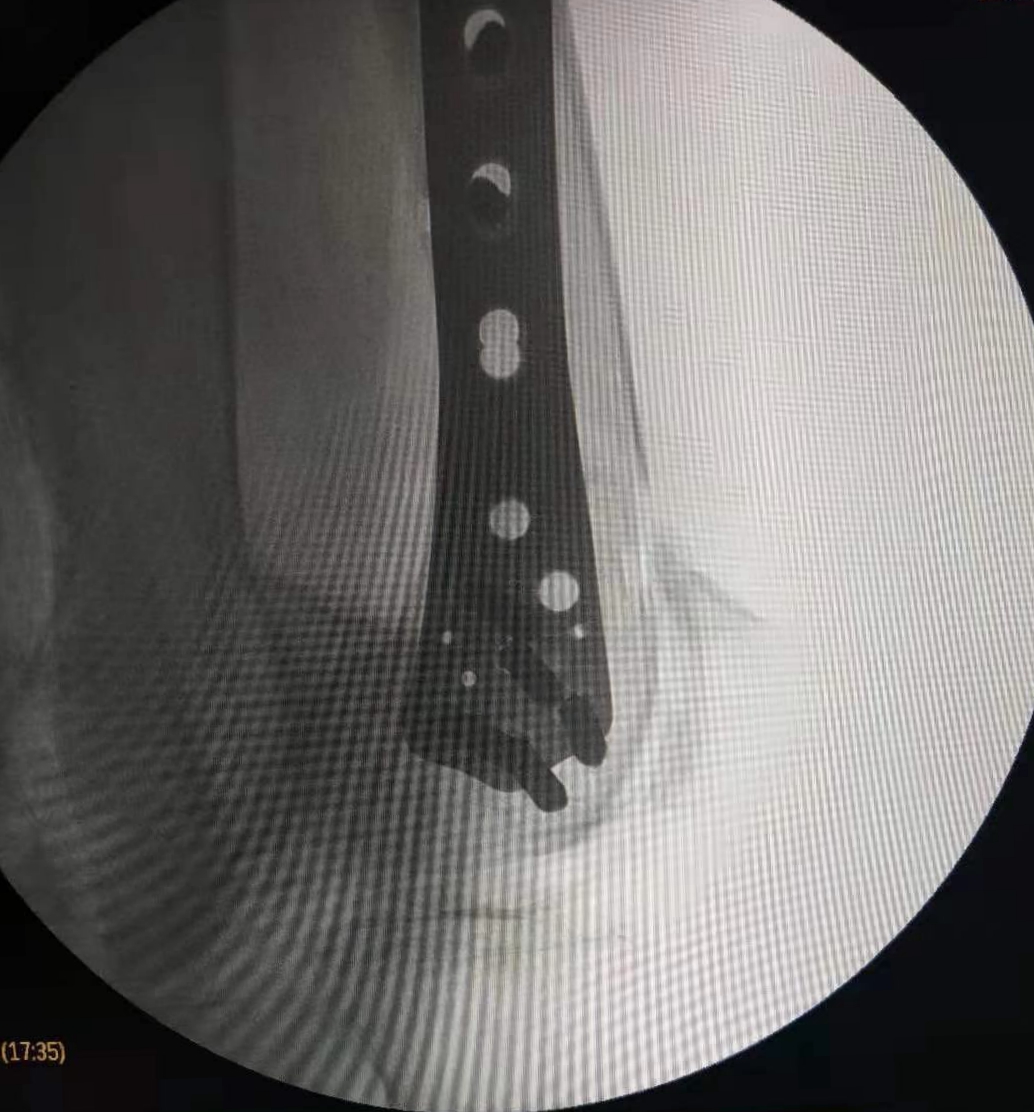

在这个寒冷的初冬,昨日市中心医院骨二科收治了一名特殊的患者,六合彩生肖 88岁高龄退休老专家,老人在家摔伤导致股骨髁上粉碎性骨折,拒绝去家附近的大医院,专程来六合彩生肖 骨二科就诊。

郭华副院长、张延平主任对病人进行了详细、全面的查体分析,因患者年龄较大,骨折严重再加上老年骨质疏松,骨折部位极易损伤后方血管,考虑患者病情的特殊性,骨二科拟行急诊手术治疗。术前,对患者进行了全面、细致的手术风险及效果评估,按照我科老年患者的优化诊疗标准流程,制定了精准的手术方案,包括风险预案、围手术期准备及护理措施,准备完成后,在急诊进行手术治疗,手术历时2小时。手术顺利、安全完成,目前患者在我科积极术后康复治疗。